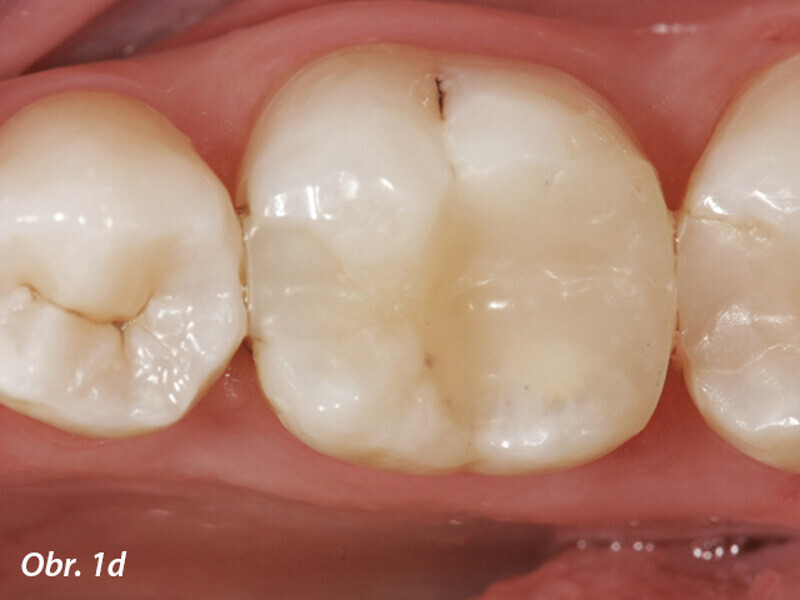

Aplikace MTA s použitím Produit Dentaires (PD) MAP System